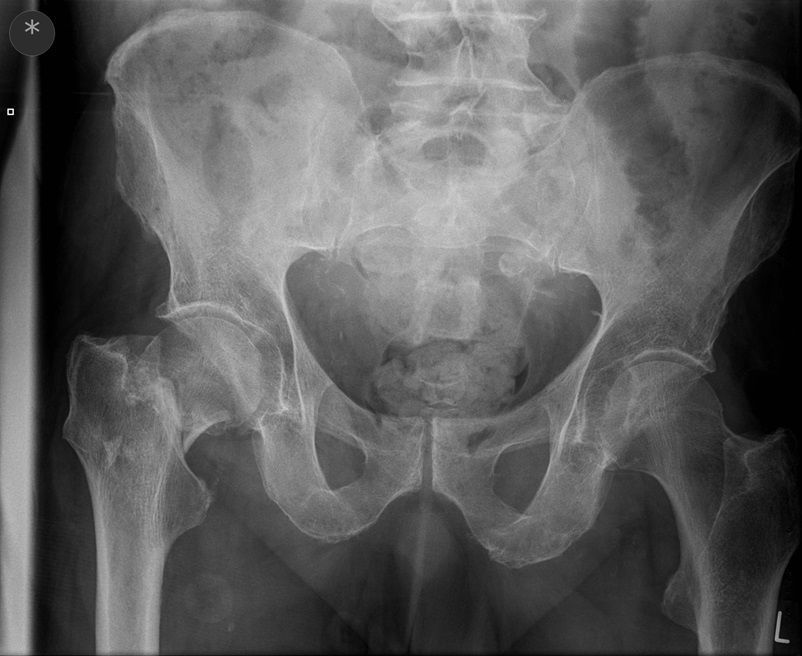

Question 3

Question

Which operation would you perform?

Answer

• THR

• Hemiarthroplasty